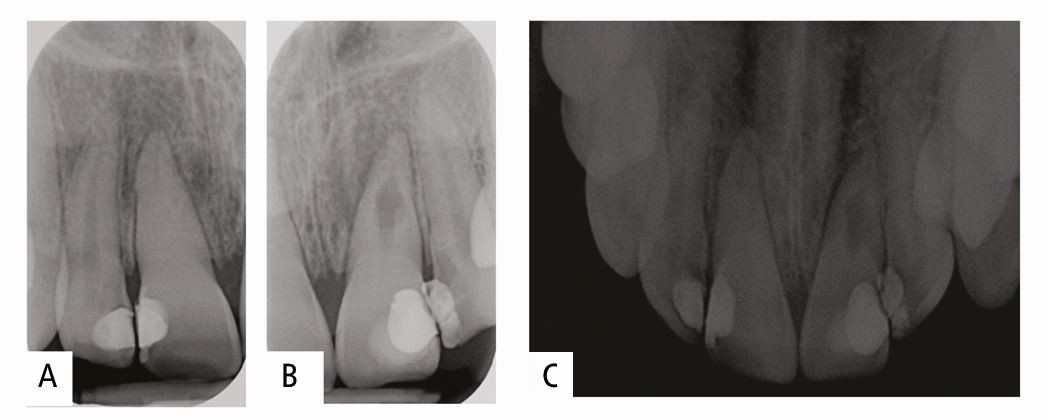

A dentally anxious 16-year-old patient presented to their general dental practitioner some years following TDI. A) Tooth 11 shows pulpal obliteration in the coronal portion of the root and an apical third root fracture. Clinically, 11 has no signs or symptoms. The radiographic appearance of 11 suggests stability because there are no alveolar changes or areas of resorption affecting the root end or horizontal root fracture area. Clinically, tooth 21 has a discharging sinus. Radiographically, there is a radiolucent lesion on the mid-third region of the root (B & C). From these images, it is difficult to ascertain whether the resorption is internal (and contained within the confines of the root canal system), internal and has perforated out with the root, or is external. Further imaging is needed for planning the appropriate treatment in this case. In this situation, because the diagnosis of 21 is unclear, it is prudent to consider onward referral prior to extirpating the pulp